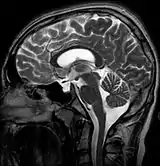

![]() | |

| MRI of Empty Sella | |